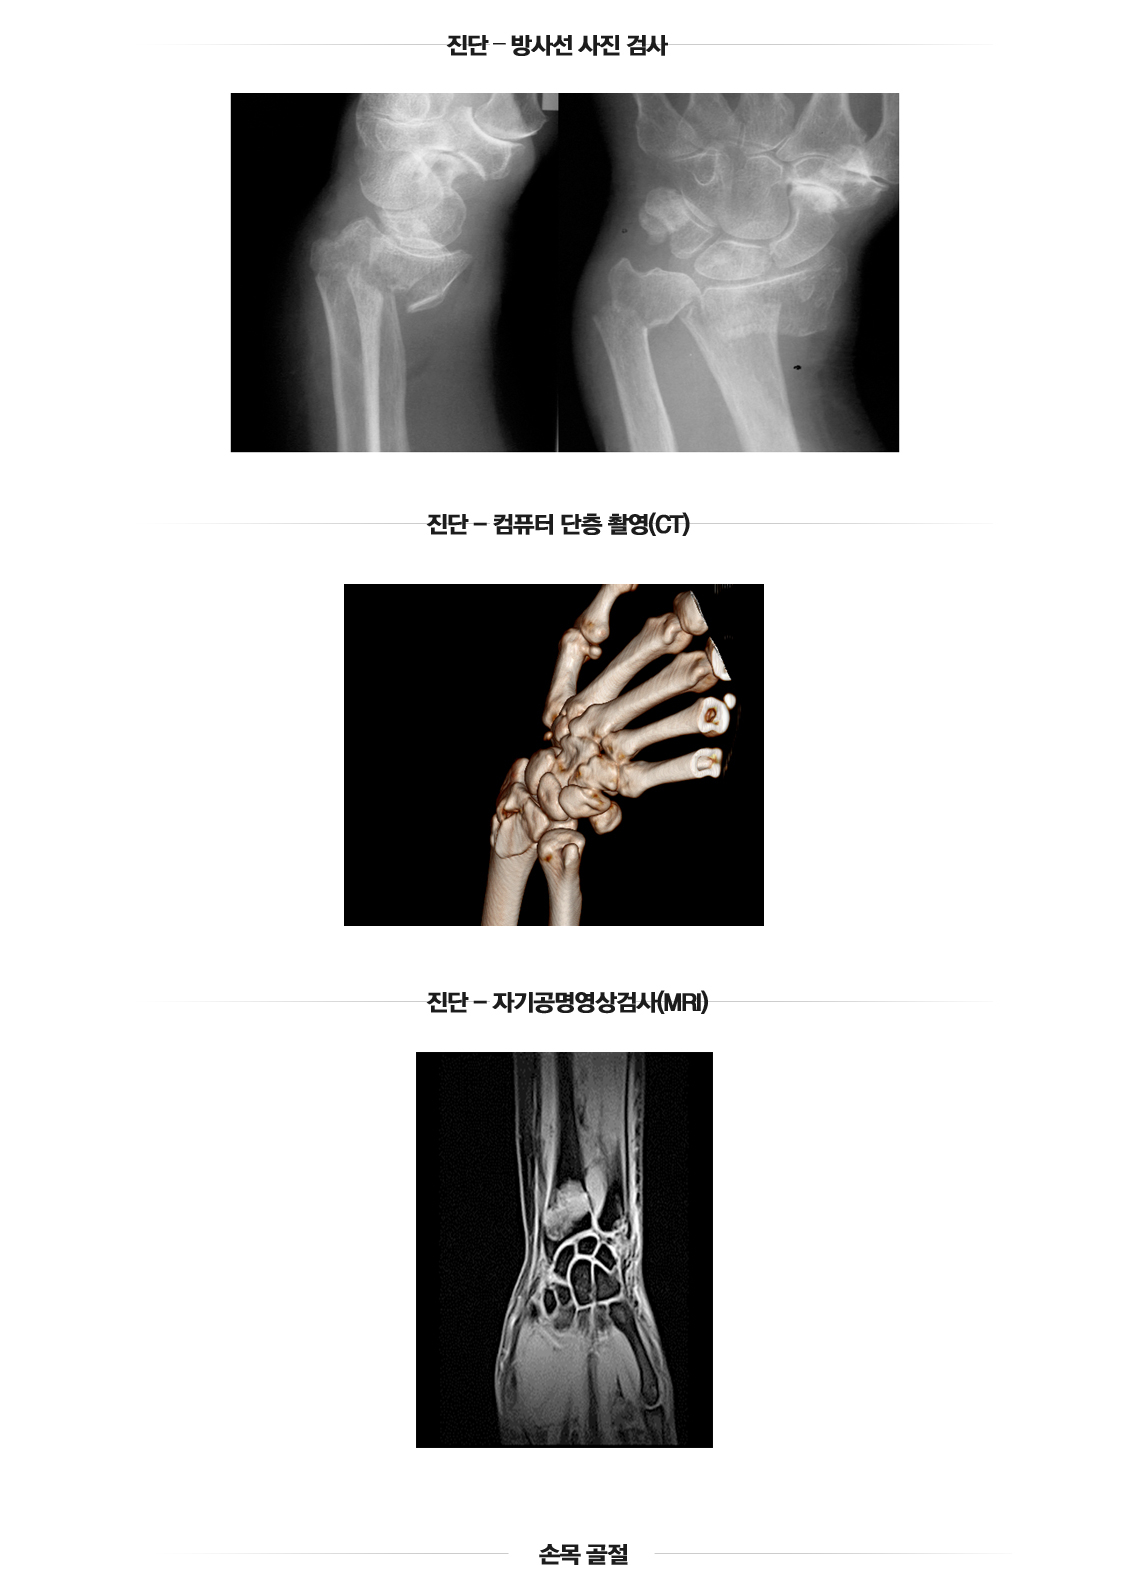

손목골절

관절주위골절(손목)

손목 골절수술

Wrist Fracture